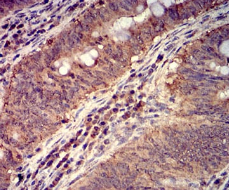

FOLR1 Mouse Monoclonal antibody[2G5C1]

AC2271 FOLR1 Mouse Monoclonal antibody[2G5C1] 100ug $367 10days

IHC    1/200 - 1/1000